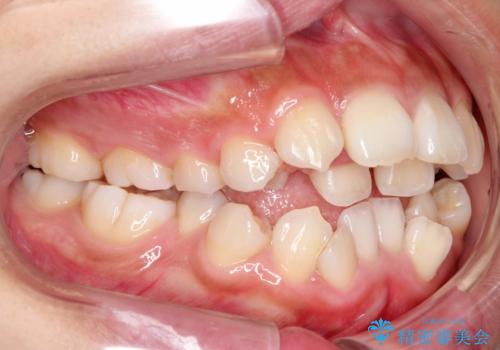

インビザラインで前歯のがたつきを目立たずに矯正治療